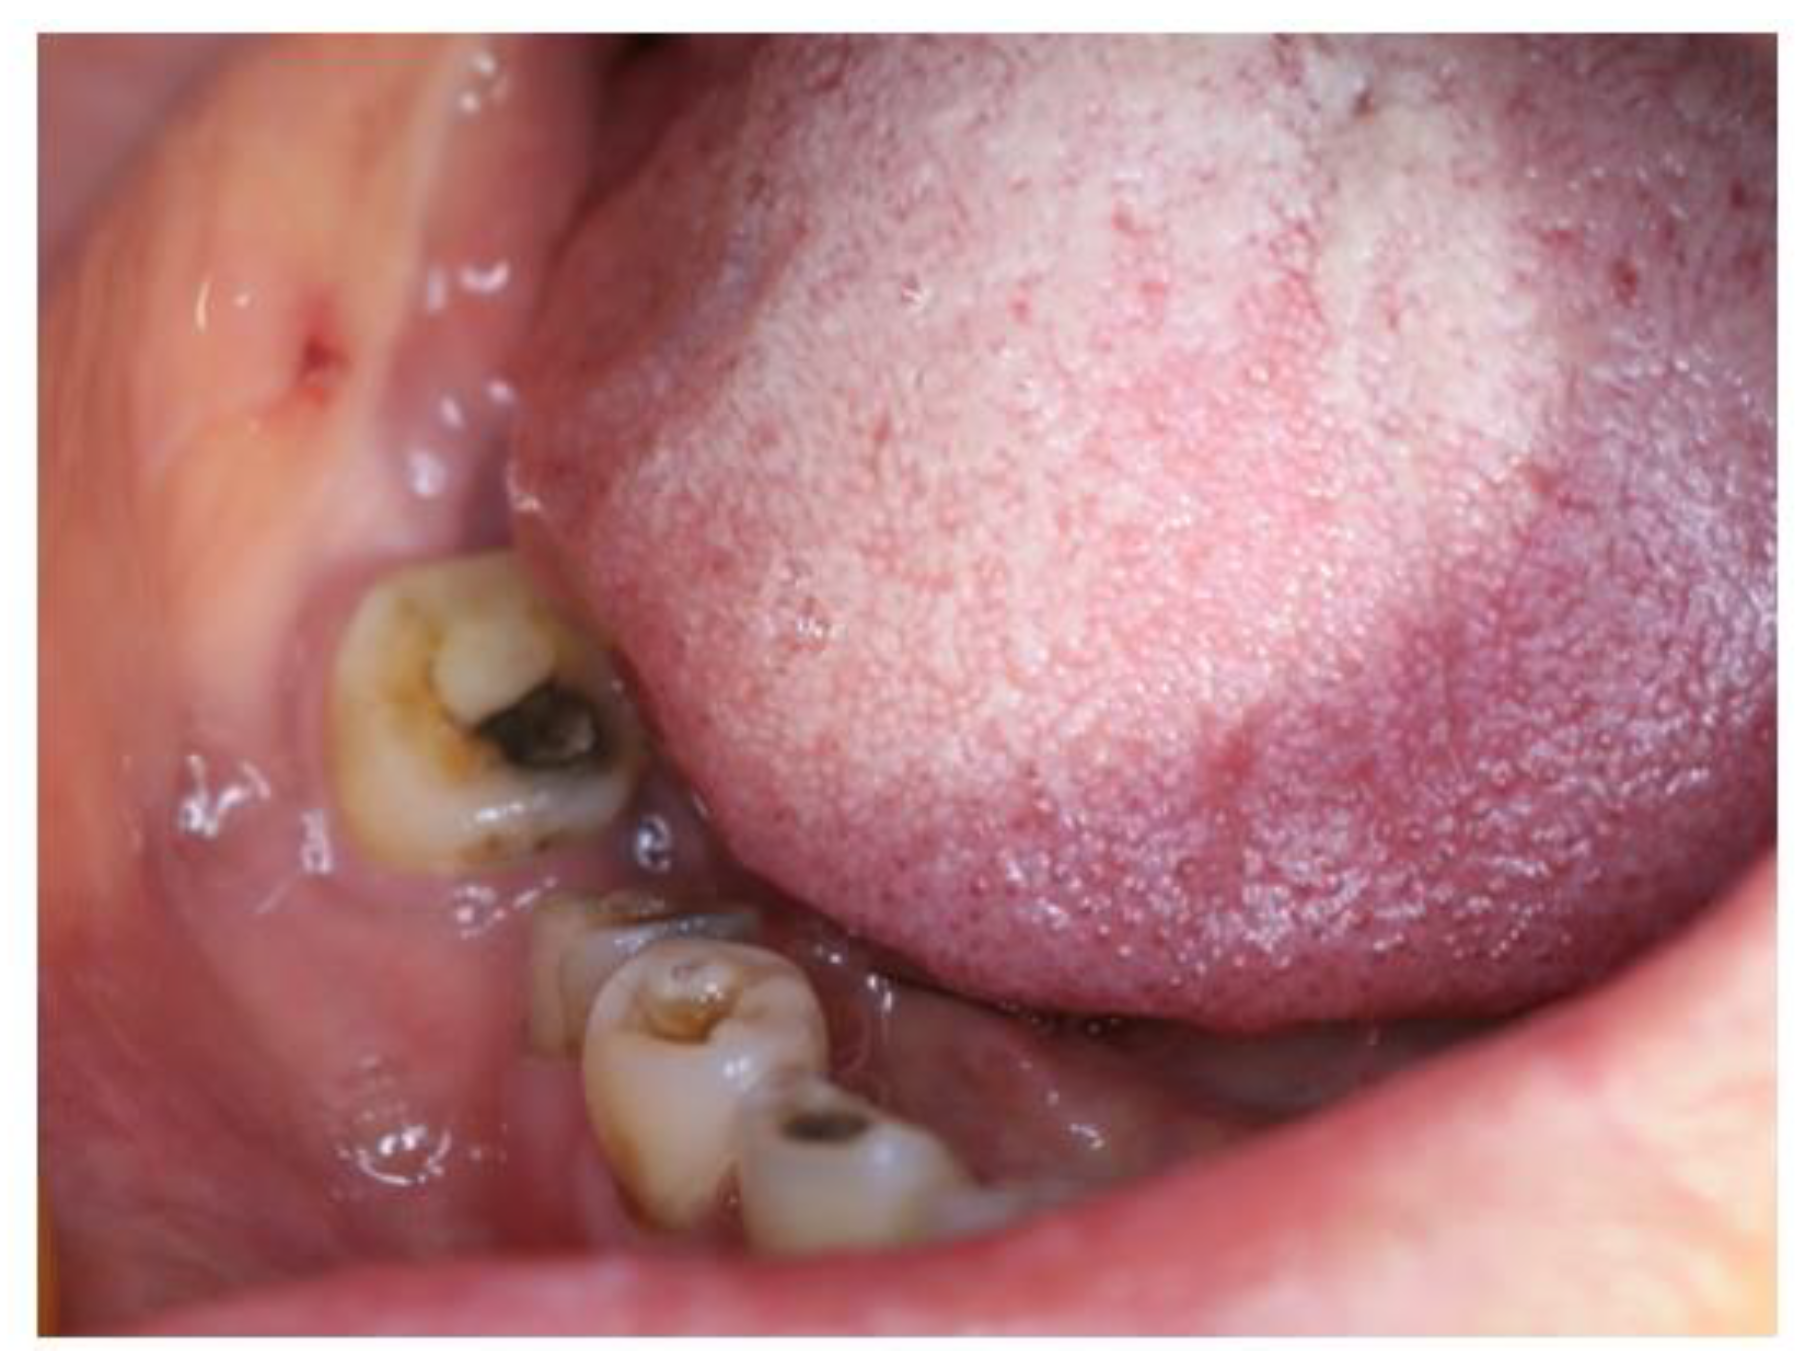

2.1. Case 1